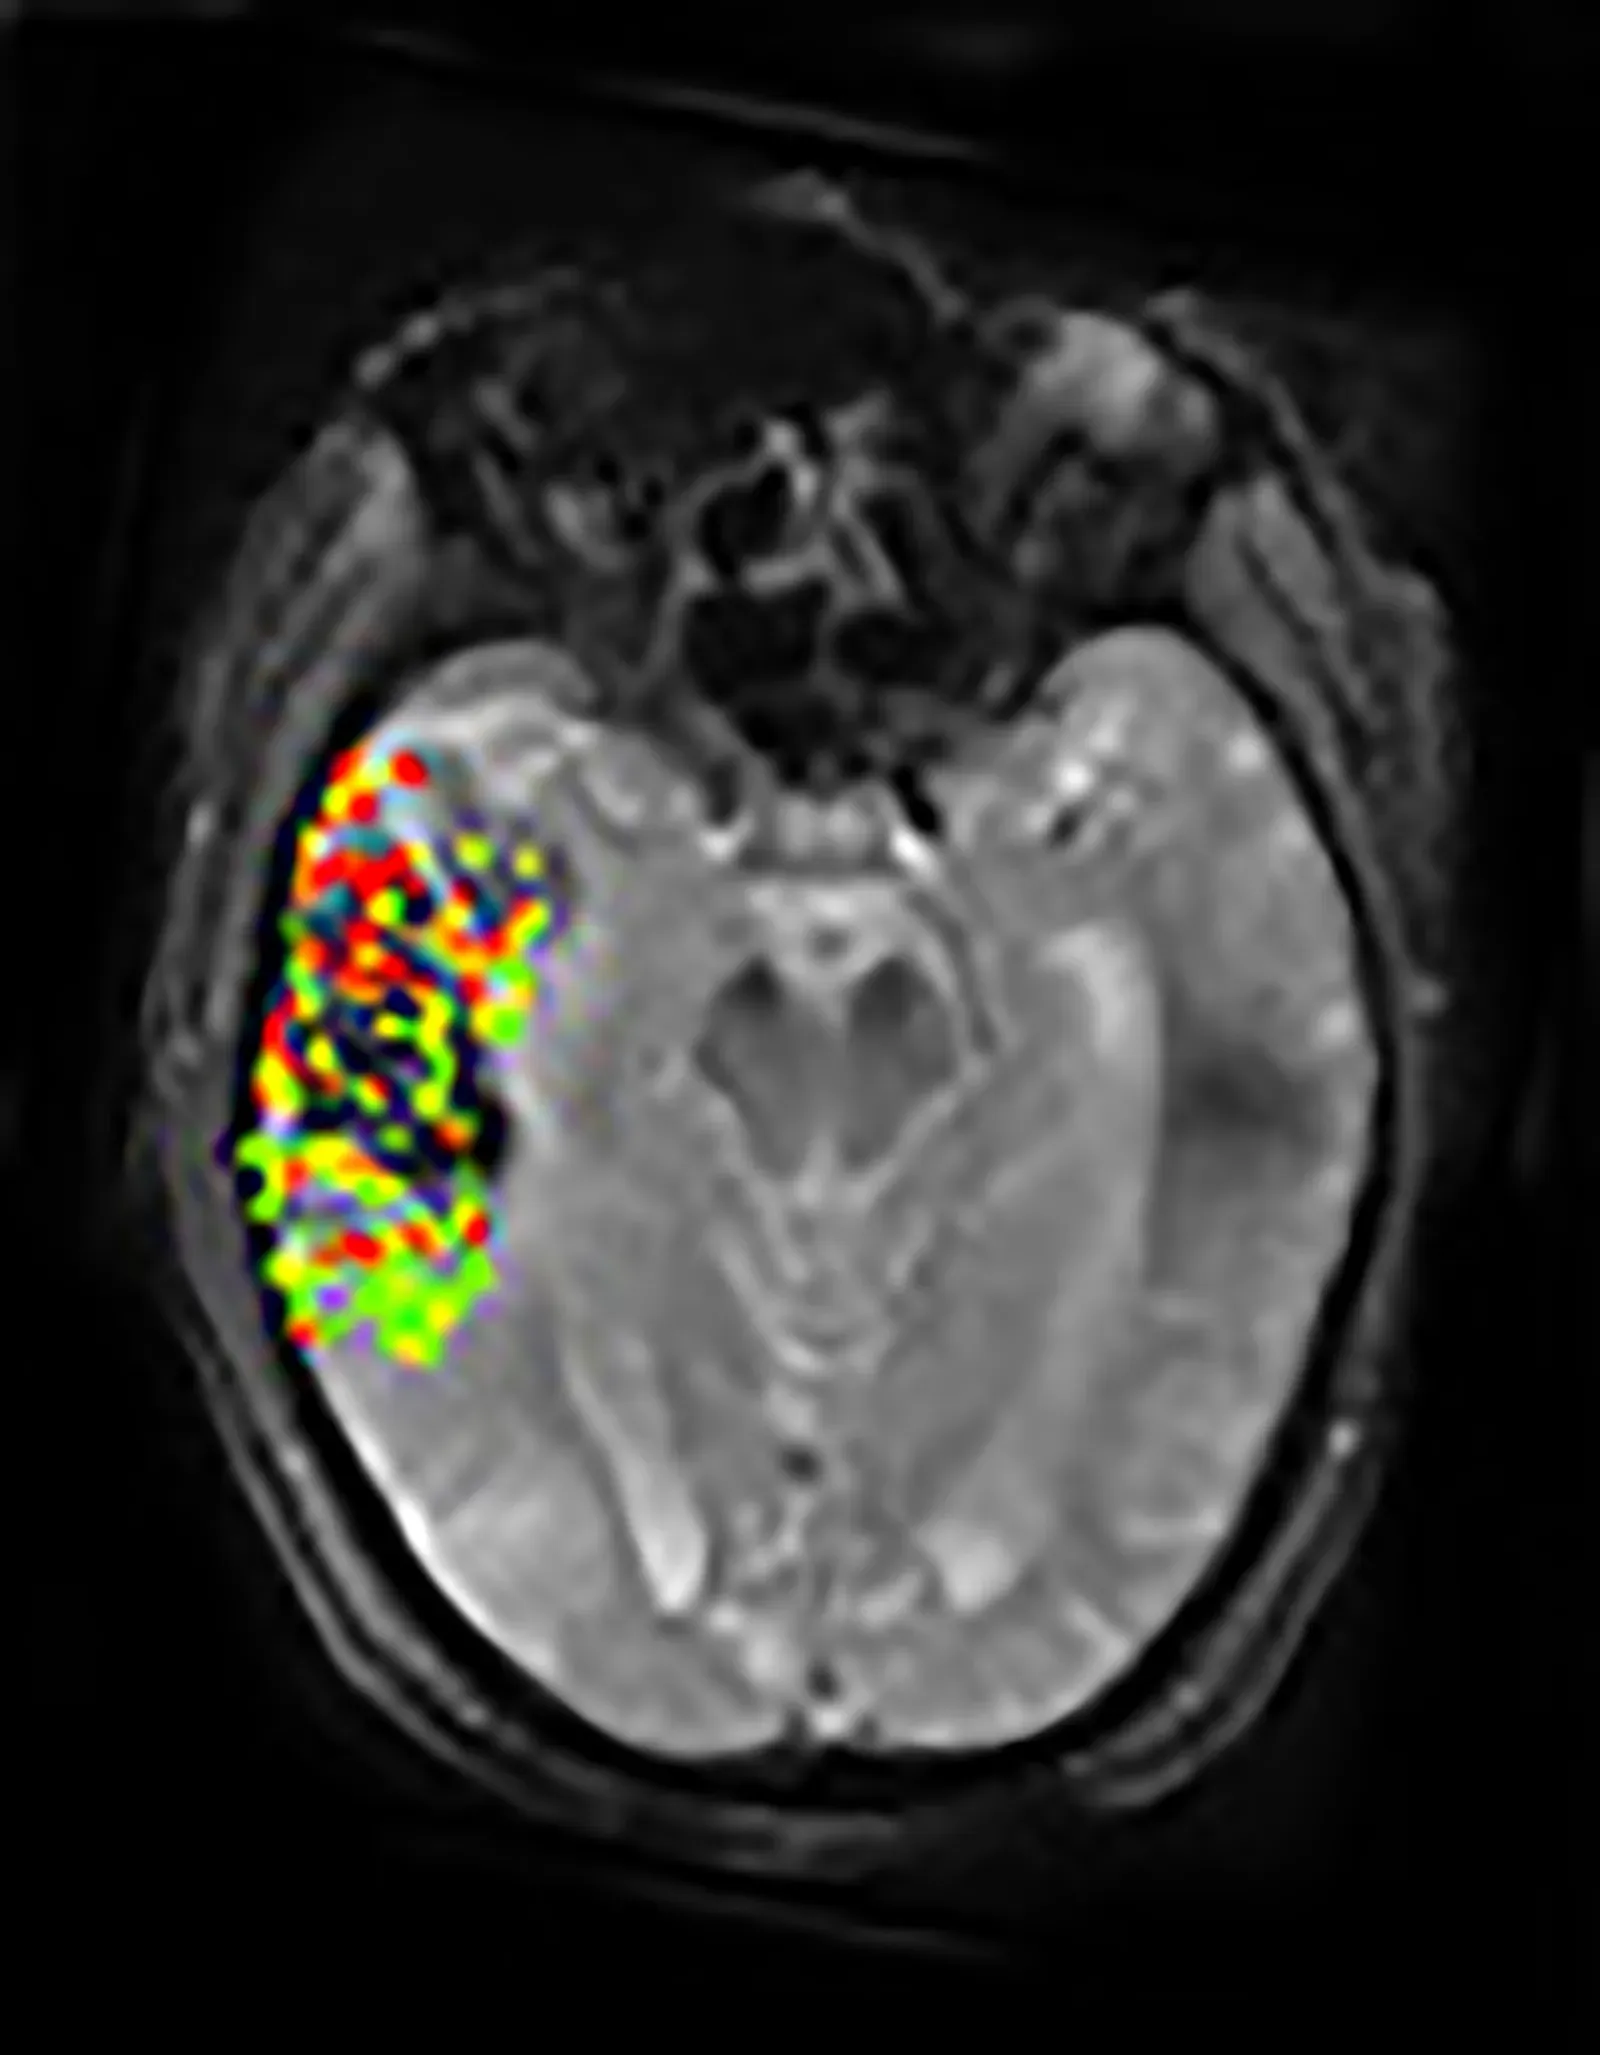

Today, powerful imaging methods like fMRI and MEG let researchers watch whole networks of brain regions coordinating as people see, hear, imagine, and dream. These tools have revealed that sensory areas are woven into loops with higher-level regions that deal with memory, expectation, and decision-making. In other words, what you sense and what you believe are constantly feeding into one another. Experiments where scientists decode what someone is looking at from brain activity alone show just how structured and interpretable these patterns can be. We are now in an era where the old philosophical hunch – reality is a mental construction – is backed by dense streams of data rather than just clever arguments.